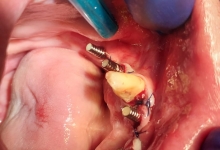

Boala parodontala are un caracter progresiv. Pentru cazurile mai grave, recomandam tratamentul parodontal chirurgical rezectiv sau regenerativ.